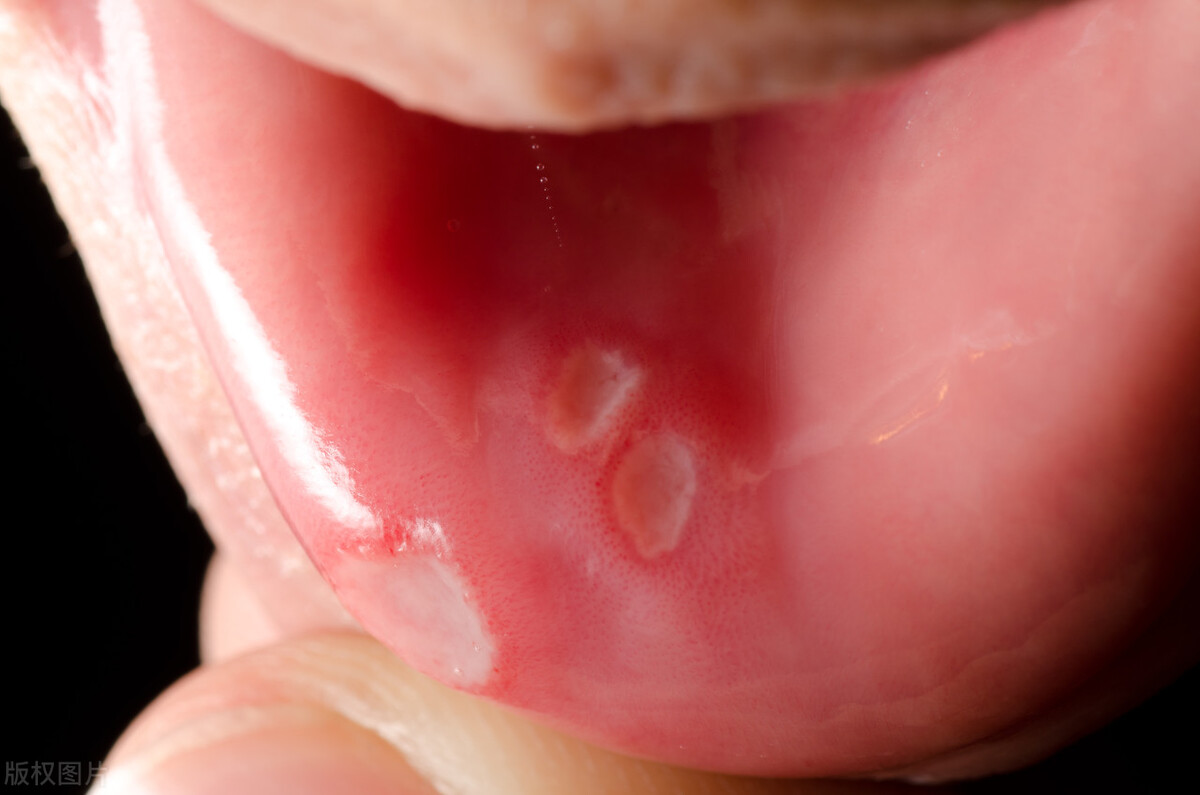

口腔溃疡属于一种口腔黏膜病变,好发于唇、颊黏膜、舌、软腭等部位,并且严重影响日常的口腔功能。

口腔溃疡往往伴随剧痛,是一种常见的口腔黏膜溃疡性损伤,俗称“口疮”。

反复发作的口腔溃疡又被称为阿弗他溃疡(RAU),其中阿弗他在希腊语中即为疼痛的意思,这也是口腔溃疡的一个显著症状所在。

1. 溃疡面积过大,最大直径超过0.5厘米;

3. 这种溃疡的形状是凹凸不平、边界不清、甚至似菜花状;